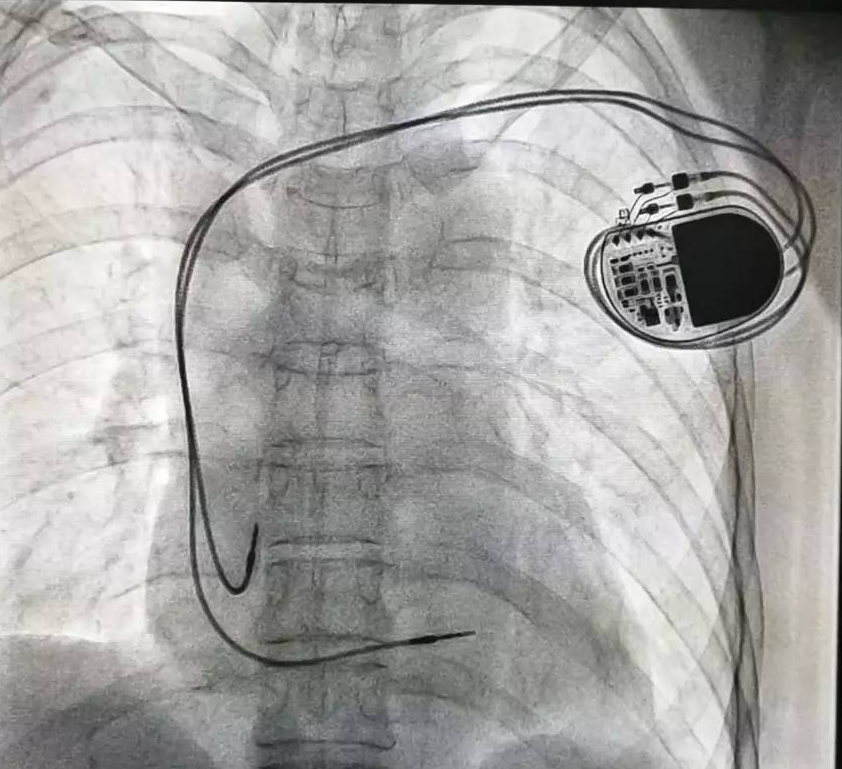

全球唯一!無(wú)線雙腔起搏器首次植入

來(lái)源:器械之家,未經(jīng)授權(quán)不得以任何形式轉(zhuǎn)載,且24小時(shí)后方可轉(zhuǎn)載。2022年2月7日雅培宣布,其在研型Aveir?雙腔無(wú)引線起搏器完成了全球首例患者植入,這也是全世界第一個(gè)雙腔無(wú)線起搏器。Aveir?DR雙腔起搏器提供右心房和心臟右心室的同步、逐次跳起搏,近80%接受起搏器治療的患者需要雙腔選擇,A